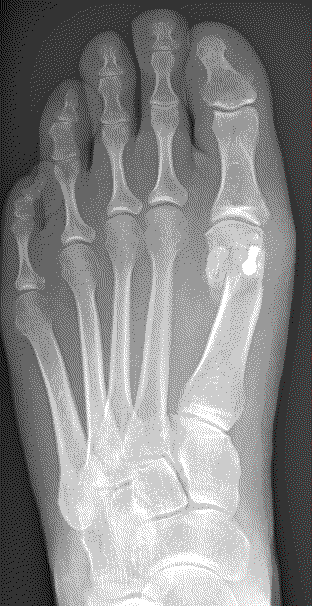

The severity of the condition is assessed by an X-ray. There is no direct correlation between the size of the deformity and the degree of symptoms experienced.

The aim of the surgery is to realign the first metatarsal almost parallel to the second metatarsal. This will move the big toe back into a straight position. This is achieved by cutting the bone. Sometimes re-balancing the soft tissue around the joint or taking a small wedge of bone out of the big toe is also required (Akin). The outcome of your operation will be dependent on the quality of your joint, the degree of arthritis present. There are numerous operations to correct bunions, but essentially, they fall into two categories: transposition and rotational procedures. Transposition osteotomies include the ‘Scarf’ and the ‘capital’. Rotational procedures include the ‘Lapidus’.

A transposition osteotomy such as a Scarf or capital osteotomy is where the bone is cut and moved across. The amount of correction available is restricted by the width of the bone. It is ideally suited to moderate deformities. In severe cases a rotational procedure such as a ‘Lapidus’ is preferred. Here a greater degree of correction is available. This operation also takes longer to heal and to settle down. Either procedure may be combined with an ‘Akin’ to help move the big toe to a straight position.